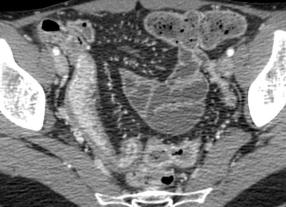

Maladie de Crohn de ileon en

coupe TDM transverse . Image epaissisement

parietale en stratification avec couche mediane

metaplasia graisseuse ( fleche rouge ) . |